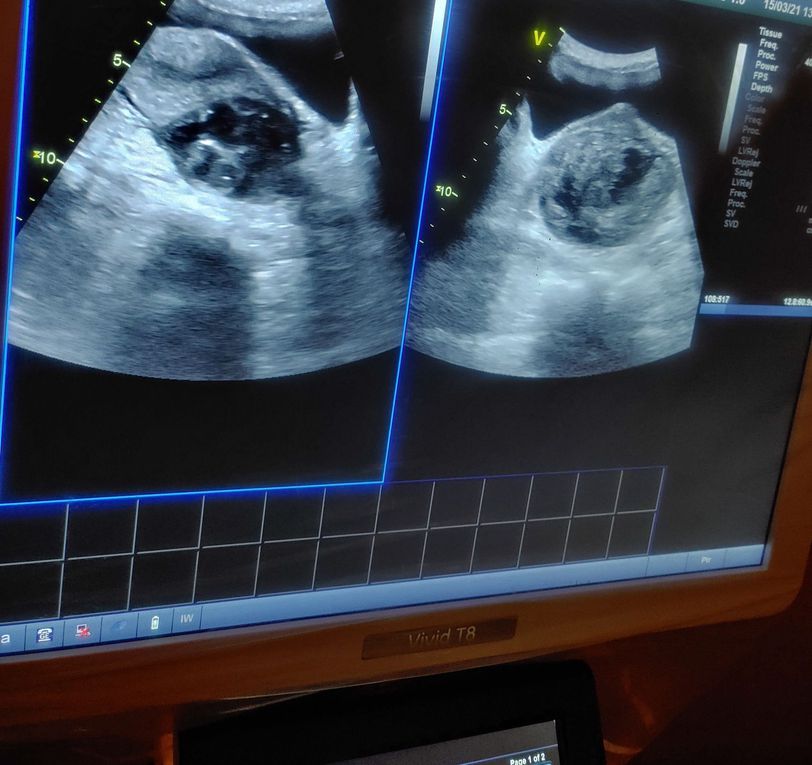

Sonetimes kidneys are abnormal

Kidney

Polycystickidneys